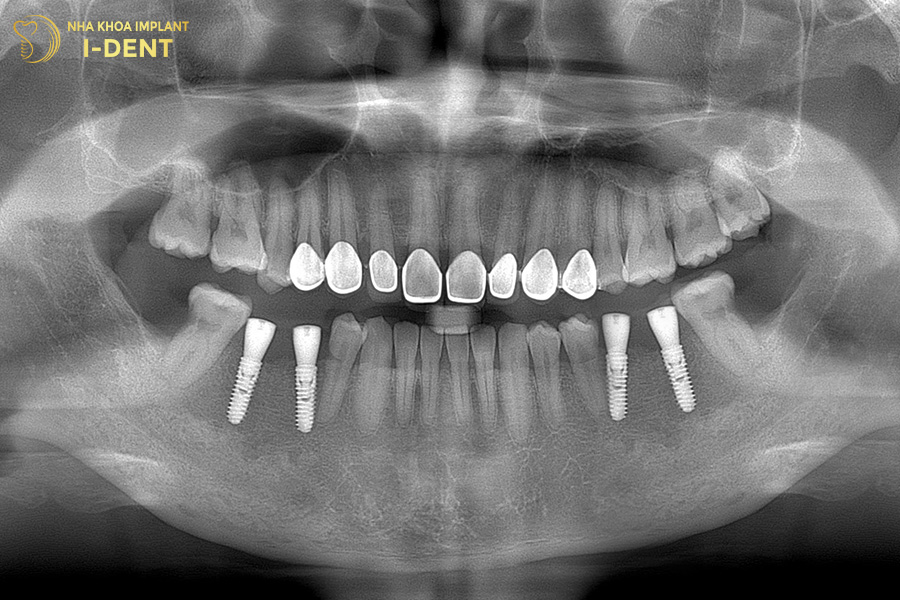

Bệnh nhân gặp nhiều khó khăn trong sinh hoạt và cuộc sống vì mất nhiều răng, hàm trên của chú Sự chỉ còn vài cái răng và cũng bị lung lay nặng. Chưa kể đến tại vị trí răng mất lâu năm còn gặp tình trạng tiêu xương nặng, cùng với đó chú còn có tiền sử mắc bệnh tiểu đường.

Tình trạng răng ban đầu của chú Trương Văn Sự

Nhận định đây là một tình trạng bệnh khá phức tạp, bác sĩ Đình Tín đã thăm khám kỹ lưỡng và đưa ra kế hoạch điều trị chi tiết. Đầu tiên, bác sĩ Tín chỉ định nhổ các răng lung lay, phẫu thuật ghép xương lớn tại những vị trí tiêu xương, sau đó mới tiến hành cấy ghép Implant toàn hàm All-on-4 cho chú Sự. Cuối cùng là phục hình toàn hàm với răng sứ Chrom-Cobalt (Mỹ) trên Implant cho chú.

Kết thúc thời gian theo dõi và điều trị, bệnh nhân đã có thể ăn uống ngon miệng hơn trước và cũng nhờ đó mà sức khỏe cũng có bước cải tiến rõ rệt.

Hình ảnh răng chú Sự sau khi cấy ghép Implant All on 4 cho hàm trên